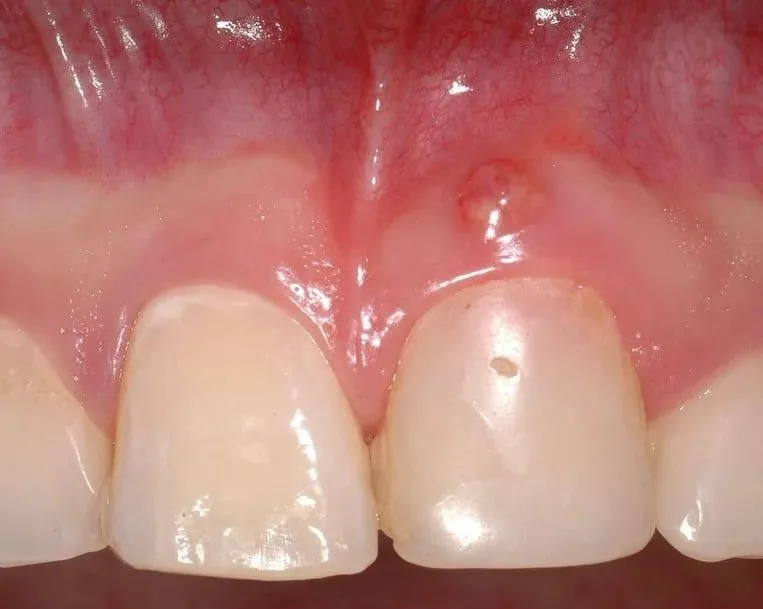

Kiedy patrzymy na dziąsła dziecka, szukamy przede wszystkim zmian wizualnych. Zdrowe dziąsła są jasnoróżowe i zwarte. W przypadku zapalenia, ich wygląd drastycznie się zmienia. Zauważymy, że dziąsła stają się zaczerwienione, często przyjmując barwę od żywoczerwonej do nawet sino-fioletowej. Co więcej, stają się obrzęknięte i rozpulchnione, tracąc swój naturalny, zwarty kontur. To wyraźny sygnał, że dzieje się coś niepokojącego.

Jednym z najbardziej charakterystycznych i niepokojących objawów zapalenia dziąseł jest krwawienie. Może ono pojawiać się spontanicznie, bez wyraźnej przyczyny, ale znacznie częściej zauważamy je podczas codziennych czynności, takich jak szczotkowanie zębów, nitkowanie, a nawet jedzenie twardszych pokarmów. Jeśli dziąsła krwawią, to niemal pewny znak, że mamy do czynienia ze stanem zapalnym i nie należy tego bagatelizować.

Innym bardzo poważnym objawem, który wymaga natychmiastowej interwencji stomatologicznej, jest pojawienie się ropnia na dziąśle. Ropień to mały pęcherzyk wypełniony ropą, który wskazuje na zaawansowany stan zapalny i nagromadzenie się infekcji. Jest to sygnał, że infekcja postępuje i może prowadzić do poważniejszych konsekwencji, jeśli nie zostanie szybko wyleczona przez specjalistę.